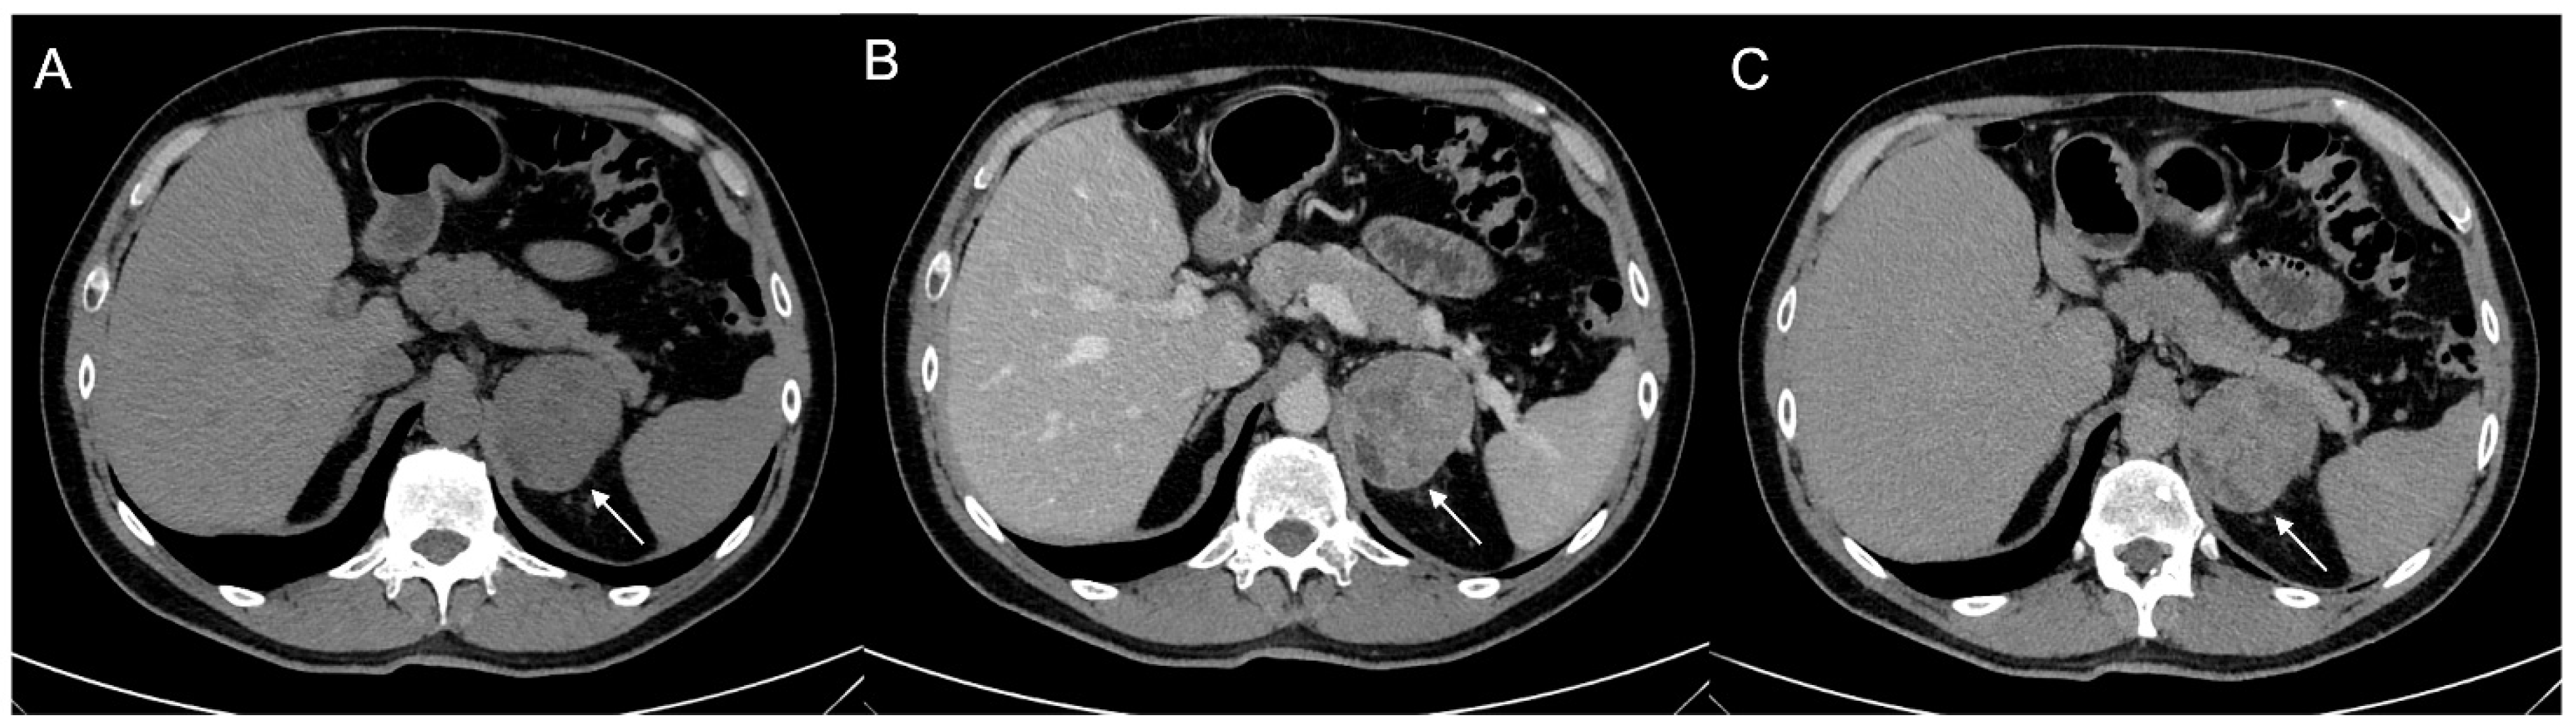

Figure 9.

Voluminous lesion (arrow) of the left adrenal gland measuring 60 × 55 mm with density value > 20 HU on basal CT (A) and inhomogeneous enhancement on venous (B) and late post-contrast phases (C) due to the presence of necrotic and cystic areas. Histological diagnosis of Adrenocortical carcinoma.